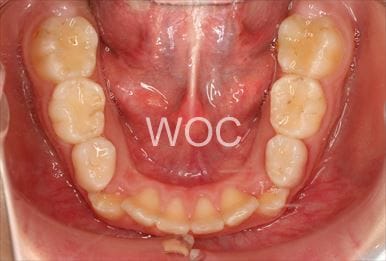

治療後1

治療後2

治療後3

治療後4

治療後5

- 年齢:23歳女性

- 主訴:出っ歯、口が閉じにくい

- 基本矯正料金:895,000円

- 治療期間:1年10ヶ月

- 非抜歯